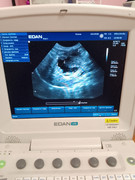

Здравствуйте, у кота по узи какое-то новообразование около поджелудочной, желчного и печени. Подскажите пожалуйста, на что это похоже? Есть только фото с экрана.

Здравствуйте! Очень сложно по картине понять, лучше короткое видео. Определяется образование неправильной формы, кистозной структуры, наиболее вероятно а поджелудочной железе, но объективно, нельзя исключить патологию желчных протоков.